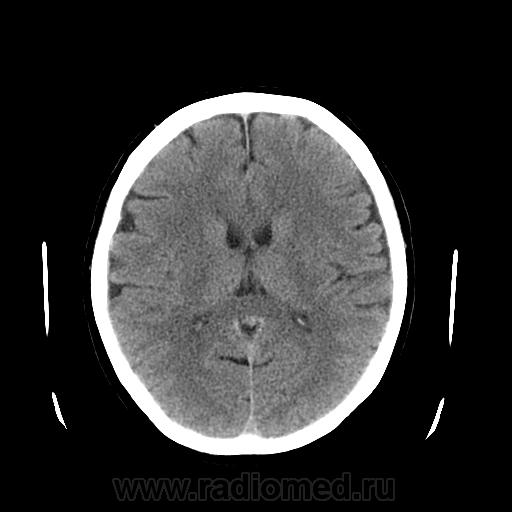

Поступила с диагнозом ОНМК. Ишемический инсульт.

Беспокоят головные боли(пульсирующего характера), судороги, потеря речи(впервые отмечала потерю речи в летом 2012года).

Не вижу КТ-признаков ОНМК. Если клиника явная, рекомендуйте МРТ

Нужно сделать КТ перфузию или МРТ

А это, что такое? не киста?

Я так думаю, что стрелочкой указаны вентральные отделы 3-го желудочка, киста межжелудочковой перегородки кпереди и выше, но при таких размерах я ее не указываю...

А то есть вероятность, что ее усердно будут лечить и контролировать :)